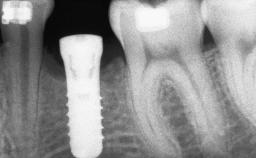

# of Teeth 14

# of Implants 12

Type of Implants One-Piece|Reduced-Diameter

Bone Augmentation Horizontal|Staged

Augmentation Materials Autogenous chips|Autogenous block(s)|Membrane

Bone Volume Deficient horizontally, requiring prior grafting